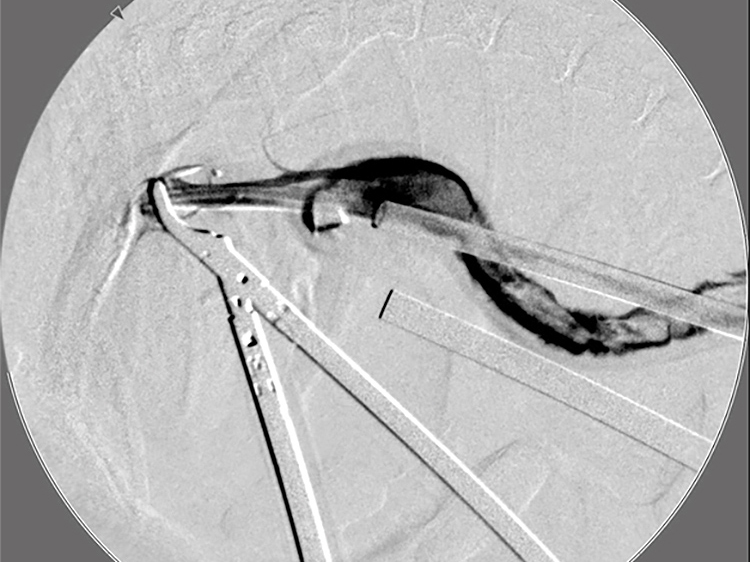

胆嚢の通路がちゃんと開通しているのか調べるために造影検査をしています。 この処置をすることで洗浄の効果と詰まりを確認することができます。

詰まりがないかを透視で確認しています。